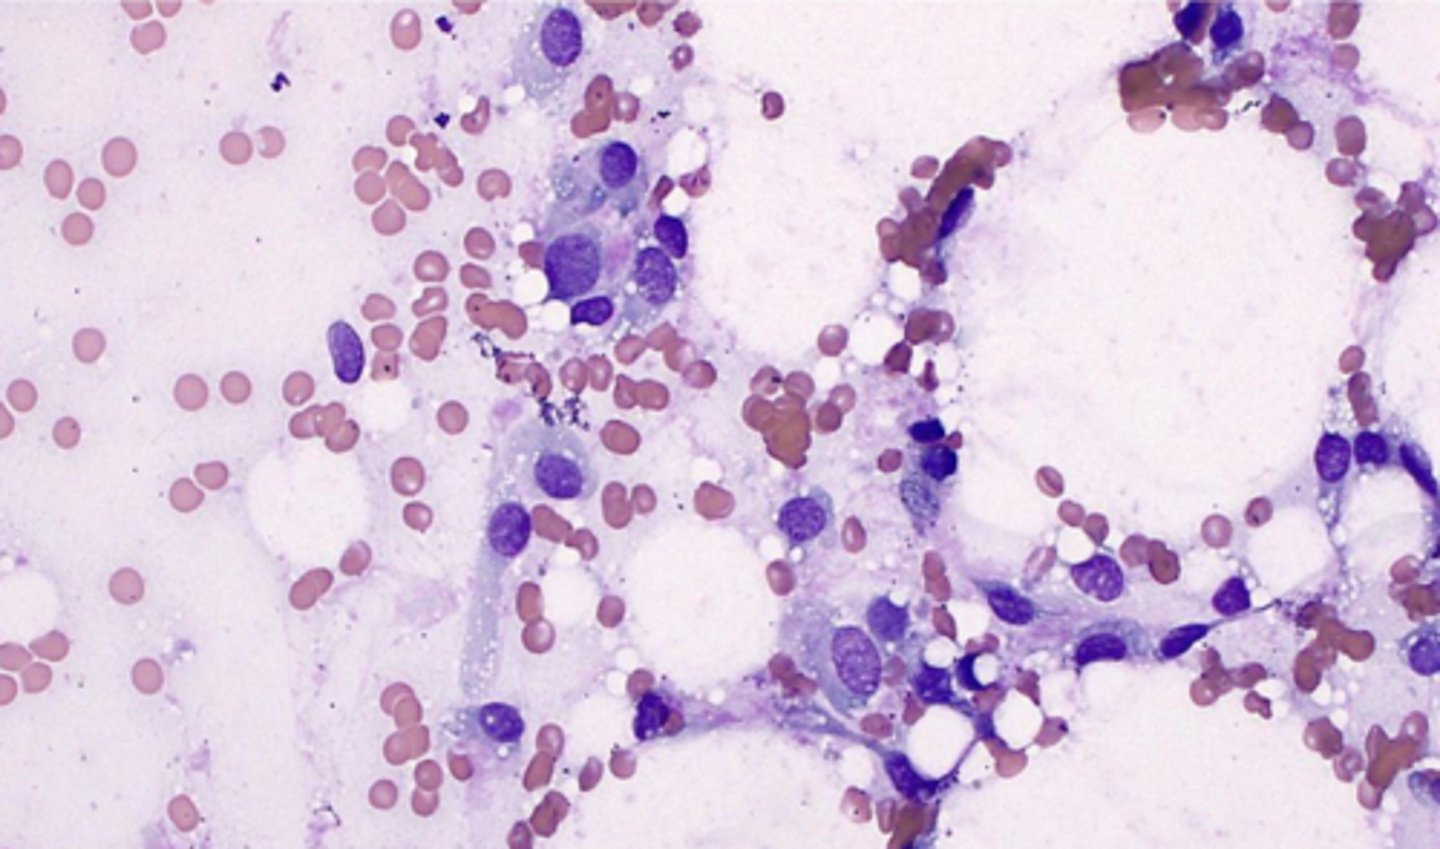

You take a FNA of a soft, movable mass within the subcutis and note this on your sample.

What is youe top differential?

Lipoma

-very common

-hard to stain slide: use new methylene blue or Oil Red O

-Lipocytes have a large, clear cytoplasm

-tiny nucleus pushed to one side